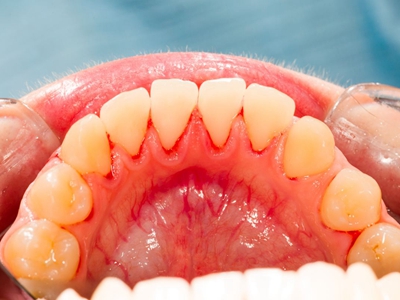

牙龈退缩下排牙龈暴露淡黄色牙根图

牙龈退缩使下排多颗牙齿的牙根暴露在外,牙根比牙冠纤细很多,色泽淡黄,牙齿间的缝隙较大。通常伴有龋齿、根面缺损、牙齿敏感等情况。